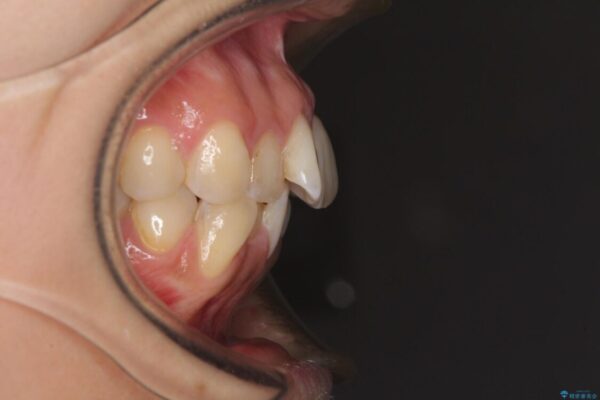

治療前

• デコボコと口元の突出感 ハーフリンガルでの抜歯矯正 治療前画像

前歯のデコボコと上顎の前突感による口の閉じにくさを気にして来院された患者様です。